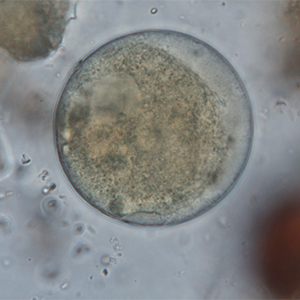

Parasitic cysts are spherical to ovoid and measure 50 to 100 µm in diameter. Their outer membrane is thick, and they have a granulomatous content. A macronucleus and a micronucleus are present, but often difficult to visualize (Strait et al., 2012). Lugol staining allows the visualization of some organelles, which are colored in dark brown. It also allows the coloration of the outer membrane in brown and of the inside of the cyst in cream.